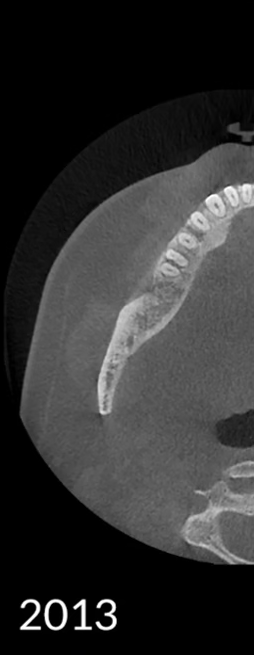

Công nghệ video của HDXWILL liên tục được cập nhật thông qua quá trình nghiên cứu không ngừng.

Một thuật toán toán học phản ánh các đặc điểm vật lý của Chụp cắt lớp vi tính chùm tia X (CBCT) và một công cụ AI tiên tiến học từ nhiều dữ liệu khác nhau sẽ phối hợp với nhau để giảm nhiễu và thể hiện cấu trúc răng rõ ràng hơn.